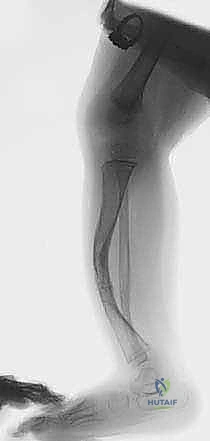

يواجه بعض الأطفال منذ لحظة الولادة أو في الأشهر الأولى من حياتهم تحديًا صحيًا فريدًا ونادرًا يُعرف في القاموس الطبي باسم "الالتحام الكاذب الخلقي في قصبة الساق". هذه الحالة المعقدة والمحبطة للآباء، والتي ترتبط في نسبة كبيرة من الحالات بمتلازمة الورم الليفي العصبي من النوع الأول (Neurofibromatosis Type 1)، تؤثر بشكل جذري على قدرة عظم قصبة الساق (Tibia) على الالتئام بشكل طبيعي بعد تعرضه لأي كسر، حتى وإن كان كَسراً مجهرياً بسيطاً.

بدلاً من تكوين نسيج عظمي جديد وقوي لالتئام الكسر كما يحدث في الحالات الطبيعية، يقوم الجسم بتكوين نسيج ليفي رخو وضعيف (نسيج عابي)، مما يؤدي إلى عدم استقرار الساق، وتقوسها، وحدوث تشوه تدريجي يمنع الطفل من المشي أو تحمل الوزن.

في حالات الالتحام الكاذب الخلقي، يولد الطفل بقصبة ساق تحمل خللاً جينياً أو بنيوياً خفياً. على الرغم من أن هذا الشذوذ يكون موجودًا منذ تكون الجنين، إلا أنه غالبًا ما يصبح واضحًا سريريًا فقط عندما يبدأ الطفل في محاولة الوقوف وتحمل الوزن، مما يؤدي إلى انحناء العظم (عادةً انحناء أمامي وحشي) ثم انكساره.

- انحناء الساق (Bowing): غالباً ما يولد الطفل بانحناء أمامي أو أمامي-جانبي (Anterolateral Bowing) في منتصف أو أسفل قصبة الساق.

- حركة غير طبيعية (مفصل كاذب): في المراحل المتقدمة، وبسبب عدم الالتئام، تتكون حركة غير طبيعية في منتصف الساق تشبه حركة المفصل، ومن هنا جاءت تسمية "الالتحام الكاذب" (Pseudarthrosis).